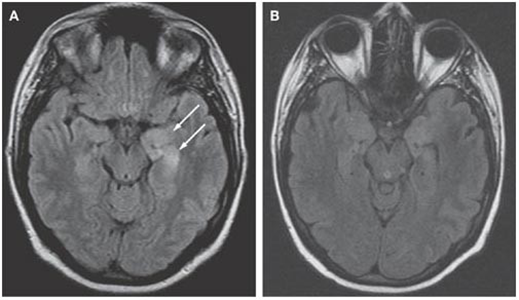

Diagnosing Anti-NMDR autoimmune encephalitis in children can be challenging, and it involves a thorough evaluation by a paediatric neurologist, including a detailed medical history, physical examination, neurological assessment, and neuroimaging, such as MRI brain scan.

MRI brain is recommended as it is more sensitive in picking up abnormal changes than CT head. Electroencephalogram (EEG) tests maybe requested to analyse your child’s brain wave signals/ pattern.

ansing, L., Tüzün, E., Ko, M. et al. A patient with encephalitis associated with NMDA receptor antibodies. Nat Rev Neurol 3, 291–296 (2007). https://doi.org/10.1038/ncpneuro0493